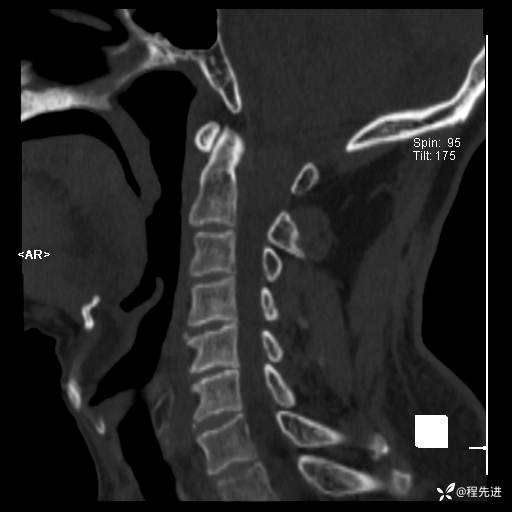

CT平扫: